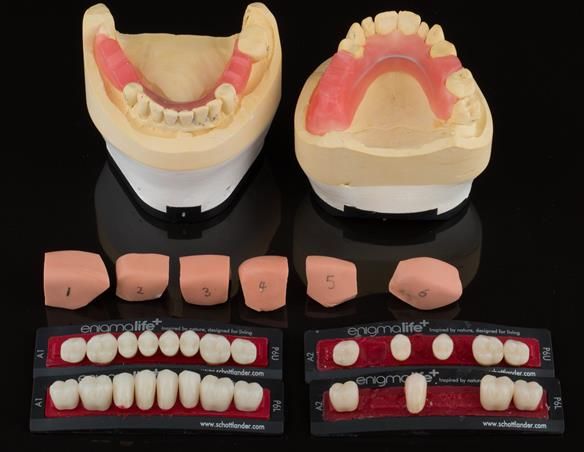

This newsletter describes in step by step detail Angela's transition through immediate partial dentures to crown supported definitive metal based dentures.

The clinical situation and treatment process is shown in detail below with photographs. I (Finlay Sutton) provided the clinical work and Rowan Garstang provided the technical work.